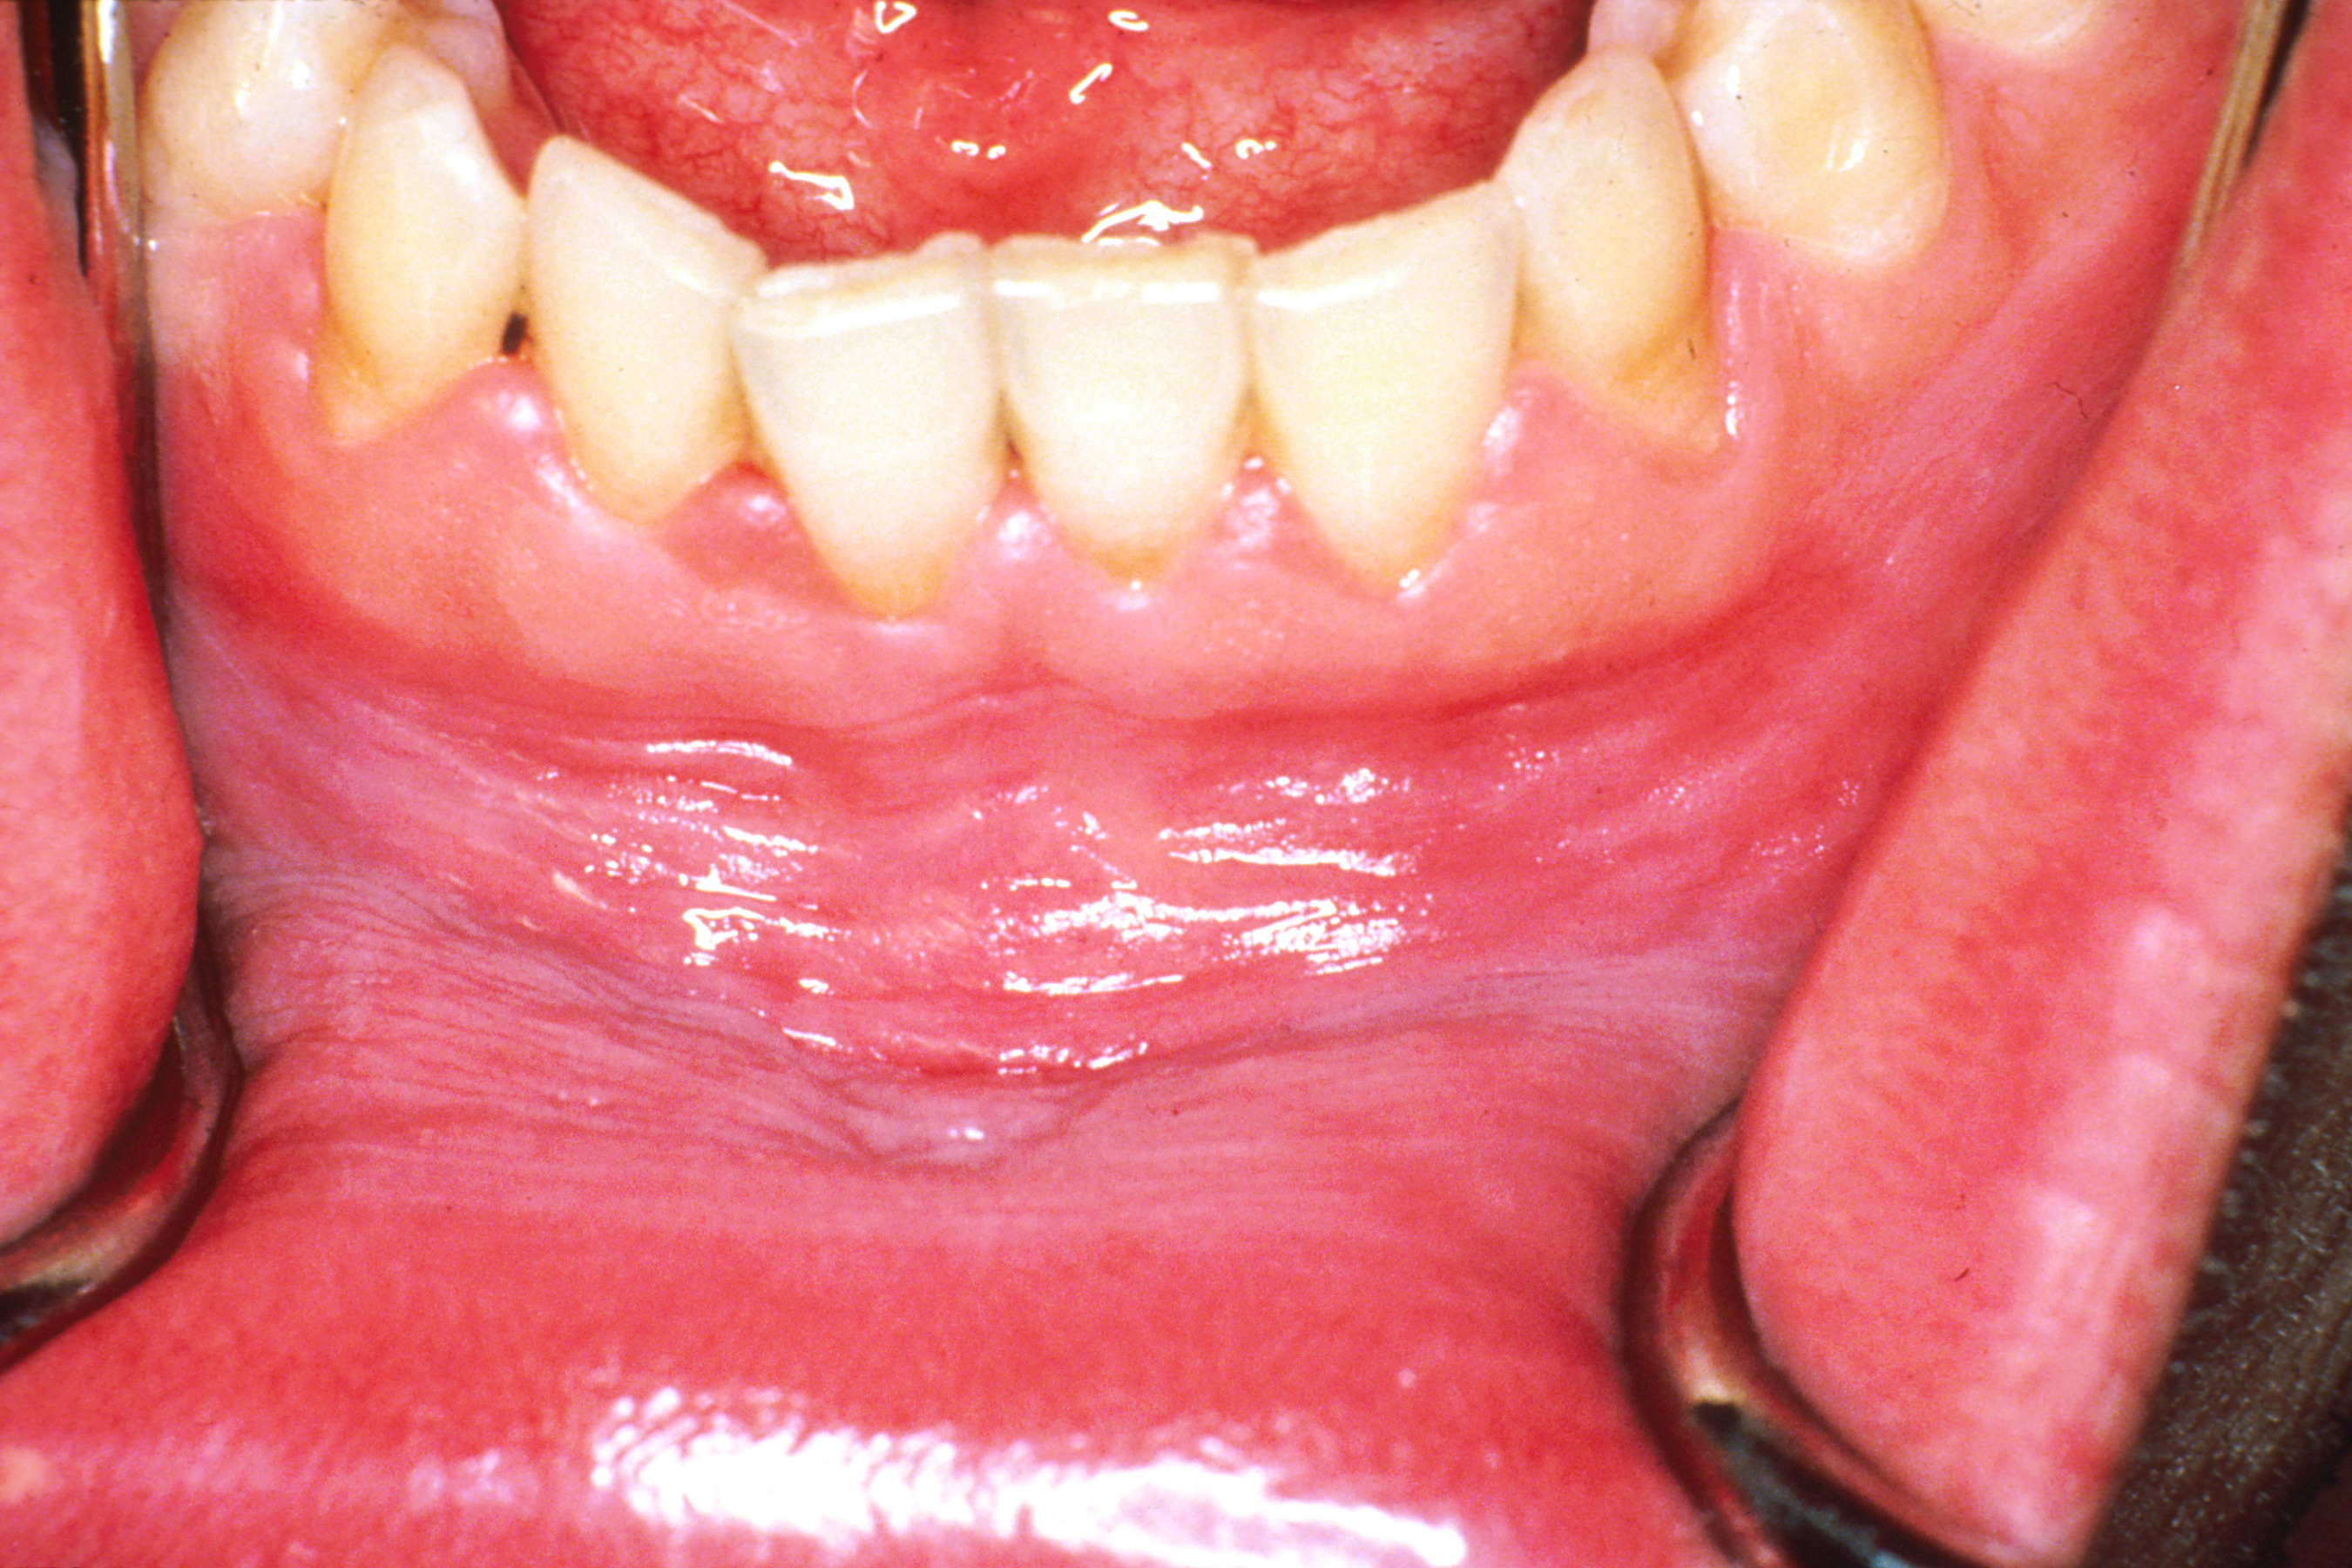

때때로 구강 바닥이나 혀 밑의 백색판증을 "설하 각화증"이라고 부르기도 한다.[23] 그러나 이는 일반적으로 특발성 백색판증과는 구별되는 별개의 임상 실체로 보편적으로 받아들여지지는 않으며,[23] 위치에 의해서만 구분된다.[10] 일반적으로 설하 각화증은 양측성이고 "썰물"이라고 묘사되는 평행 주름진 표면 질감을 가지고 있다.[10]2. 1. 4. 칸디다 백색판증